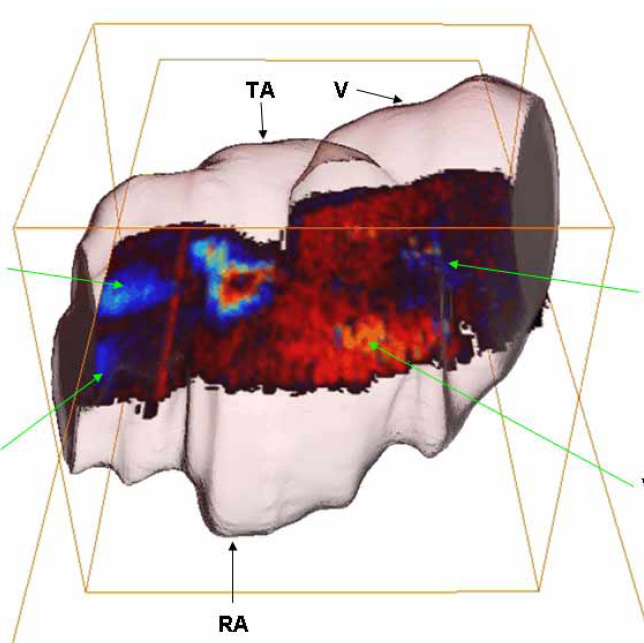

Live imaging of blood flow in mammalian embryos using Doppler swept-source optical coherence tomography

I. V. Larina, et al., Journal of Biomedical Optics, 13 (6), 2008.

Doppler optical cardiogram gated 2D color flow imaging at 1000 fps and 4D in vivo visualization of embryonic heart at 45 fps on a swept source OCT system

A. Mariampillai, et al., Optics Express, 15 (4), 2007.